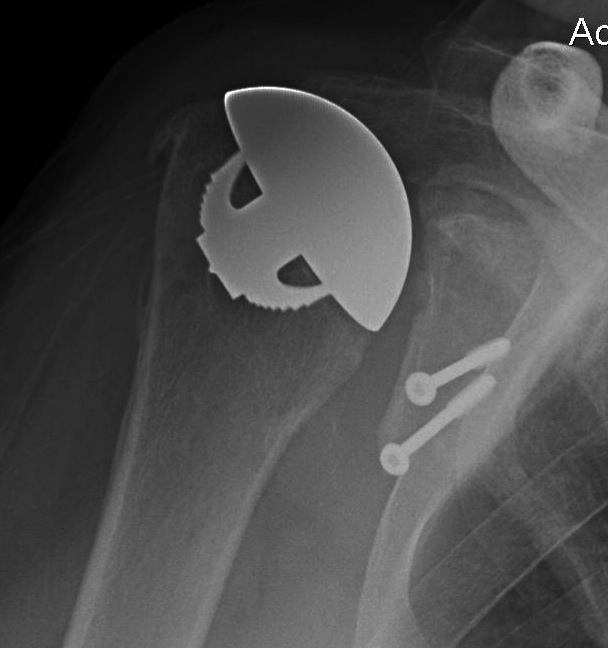

Aseptic loosening

TSR Loose glenoidaTSA loose glenoid

Glenoid Component LooseningHumeral resurface loose

Incidence

Schoch et al. JSES 2019

- 492 aTSA at 5 year follow up

- 308 (63%) had no radiolucent lines

- 184 (37%) had peri-glenoid lucency

- those with glenoid lucency had decreased ROM and patient-reported outcomes